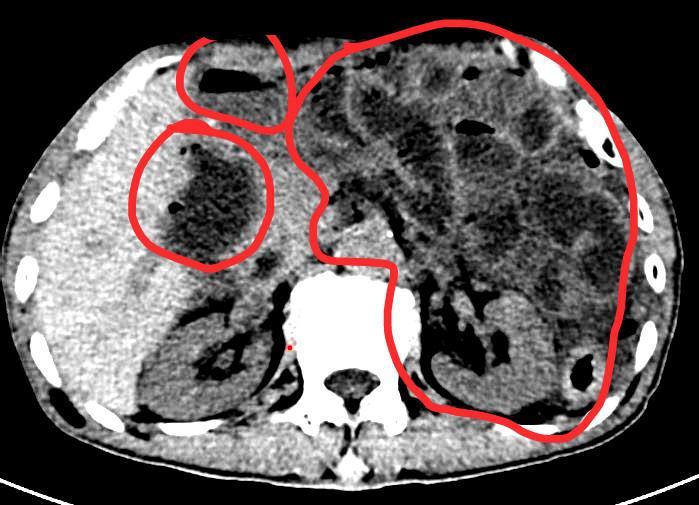

宋先生腹腔内的大便

因为实在太疼,宋先生随后前往温州医科大学附属第二医院急诊科就诊。经医院检查CT显示,宋先生乙状结肠壁穿孔及气体影渗出,腹部肠腔内容物潴留。经过积极的术前准备,医生果断紧急剖腹探查,发现宋先生直肠乙状结肠下段对系膜缘见一直径约4cm的破口,同时由于他就诊不及时,导致整个腹腔内充满大量粪便,肠管、肠系膜及大网膜等多处已形成黄色脓苔,生命危在旦夕。